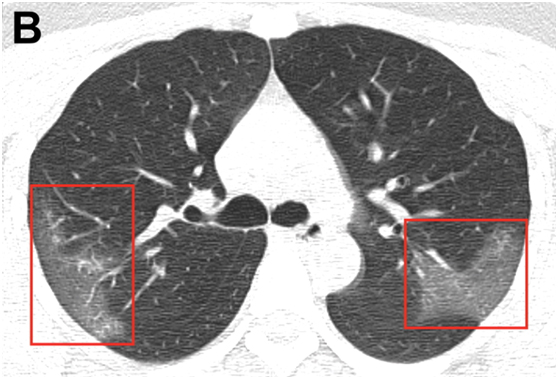

圖B:經(jīng)過三天的治療,并結(jié)合干擾素吸入,該患者臨床表現(xiàn)更差,復(fù)查胸部CT顯示右上葉后段及左上葉頂端后段進行性毛玻璃樣混濁。

研究指出,影像學檢查是2019-nCoV診斷的關(guān)鍵組成部分。雙側(cè)對稱的肺周混濁是2019新型冠狀病毒肺炎的常見CT表現(xiàn)。早期疾病識別不僅對及時治療至關(guān)重要,而且對患者隔離和有效的公共衛(wèi)生控制和應(yīng)對也至關(guān)重要。